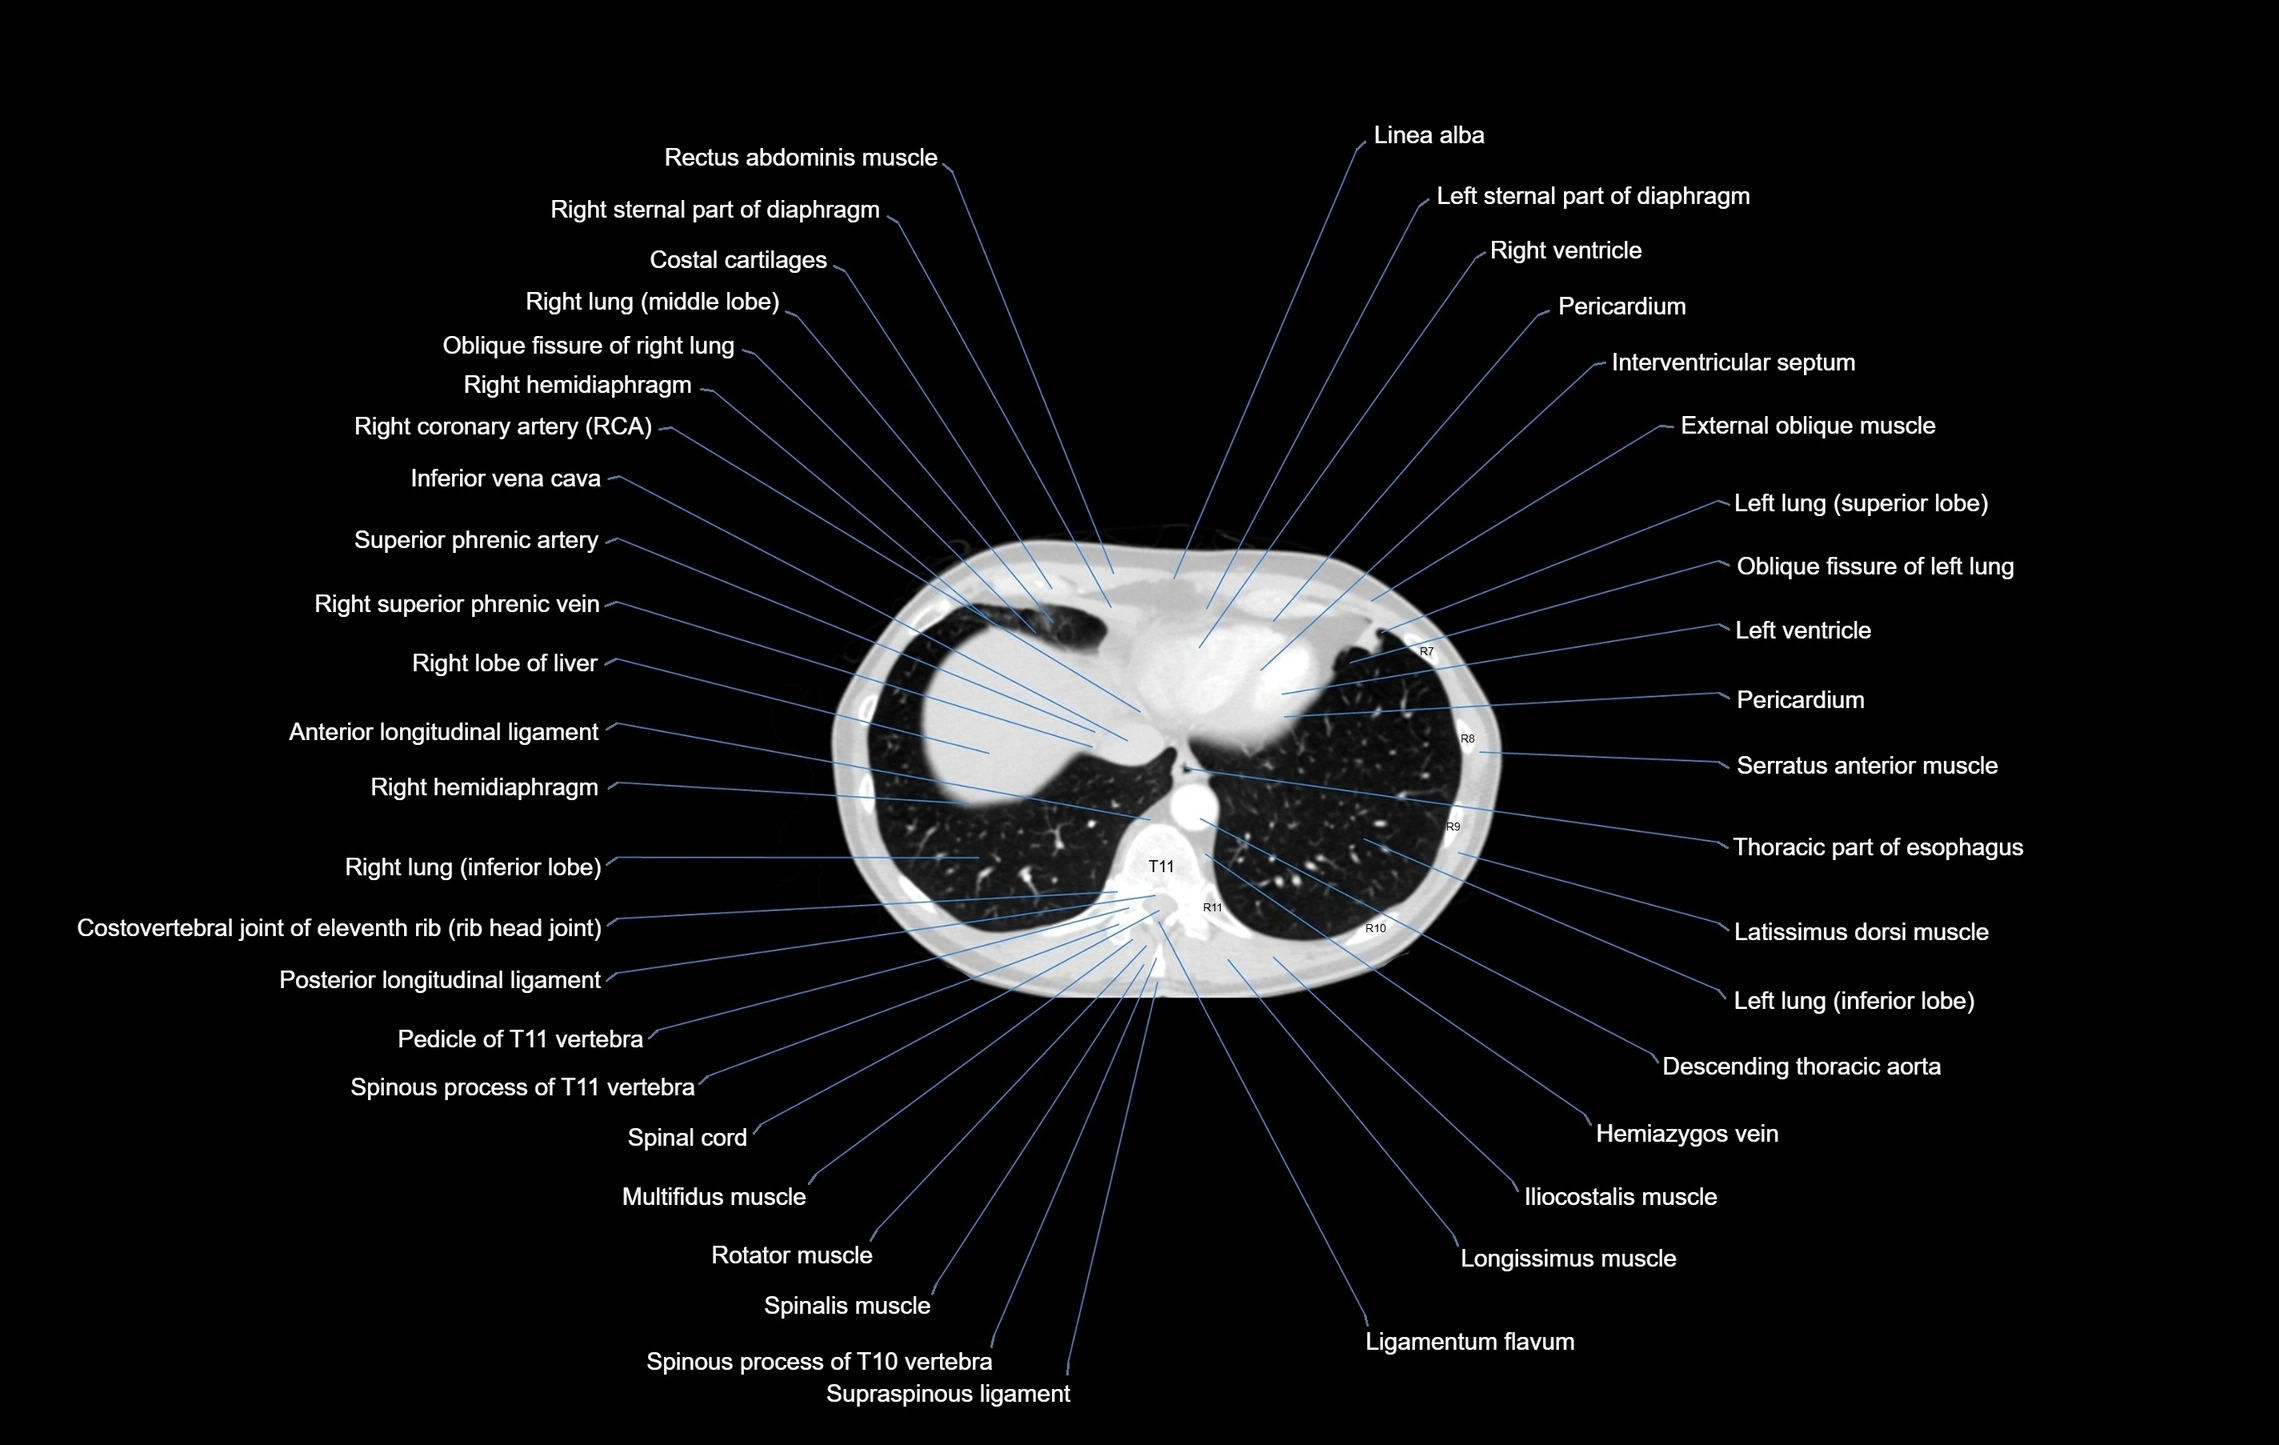

CT images